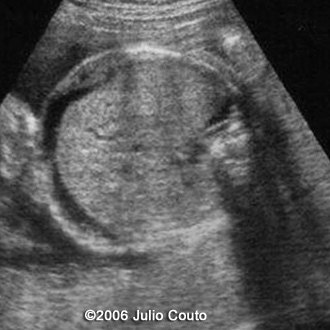

This a second-trimester-fetus with toxoplasmosis infection.

Note the cerebral calcifications